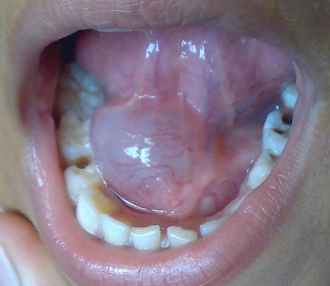

ranula

large mass in floor of mouth from sublingual gland

surgical removal, marsuopialization

treatment forr RANULA